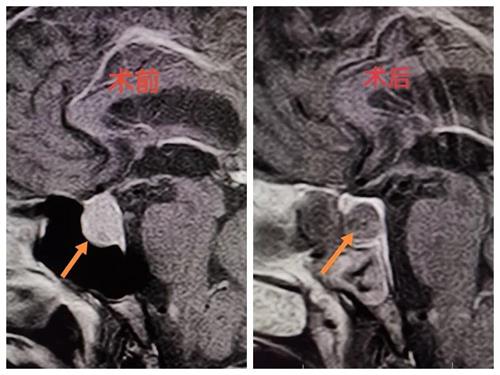

日前,井陉县医院外一科成功完成一例神经内镜下经鼻蝶垂体瘤切除术。此手术应用目前最先进的假包膜外切除技术,术后内分泌指标达到治愈级水平,标志着我院垂体瘤手术技术取得新的突破。

术后复查增强MR见瘤体完整切除,复查生长激素水平达到治愈级水平。李大叔心悸,胸闷气短症状明显好转,3天后便下地活动。